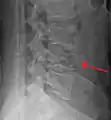

- A burst fracture of L4 as seen on plane X ray

- A burst fracture of L4 as seen one plane X ray